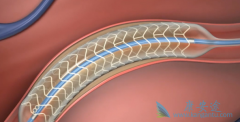

不少人都听过心脏支架手术,这种手术堪称是当代心脏病学最伟大的一项发明。你知道这个小小的支架是怎么放到心脏里去的吗? 心脏支架 是通过介入手术的方式植入到人体的,我们可以从心脏介入手术可是说起,这样更好理解。心脏介入原理其实并不复杂。 ...

心脏支架 选哪种?放最好的支架?还是放最贵的支架?今天就给大家答疑解惑!心脏支架由具有强支撑力的合金制成,不同厂家支架的金属结构略有差别。心脏支架没有植入体内之前,包裹在球囊外面。植入时给球囊加压,支架打开至预定直径,使支架与血管壁完 ...

心脏支架手术 ,又被称之为冠状动脉支架植入手术,目前是冠心病的最重要治疗方式之一,手术期间需要在患者的冠状动脉处放置支架以拓宽狭窄的血管壁,使冠状动脉复通并使血液正常的流动,目前在三种情况下建议尽快进行心脏支架手术。情况一:患者的血管 ...